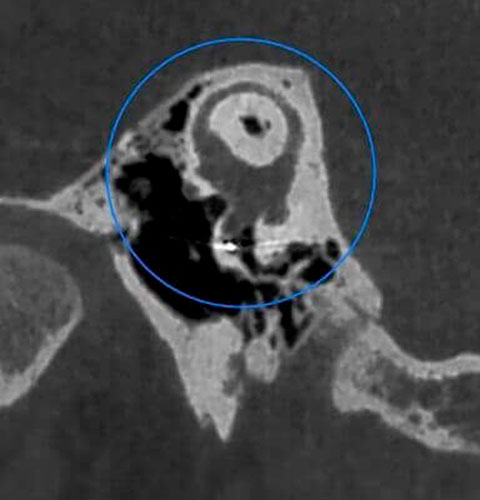

Veja exemplos de diagnósticos de imagem